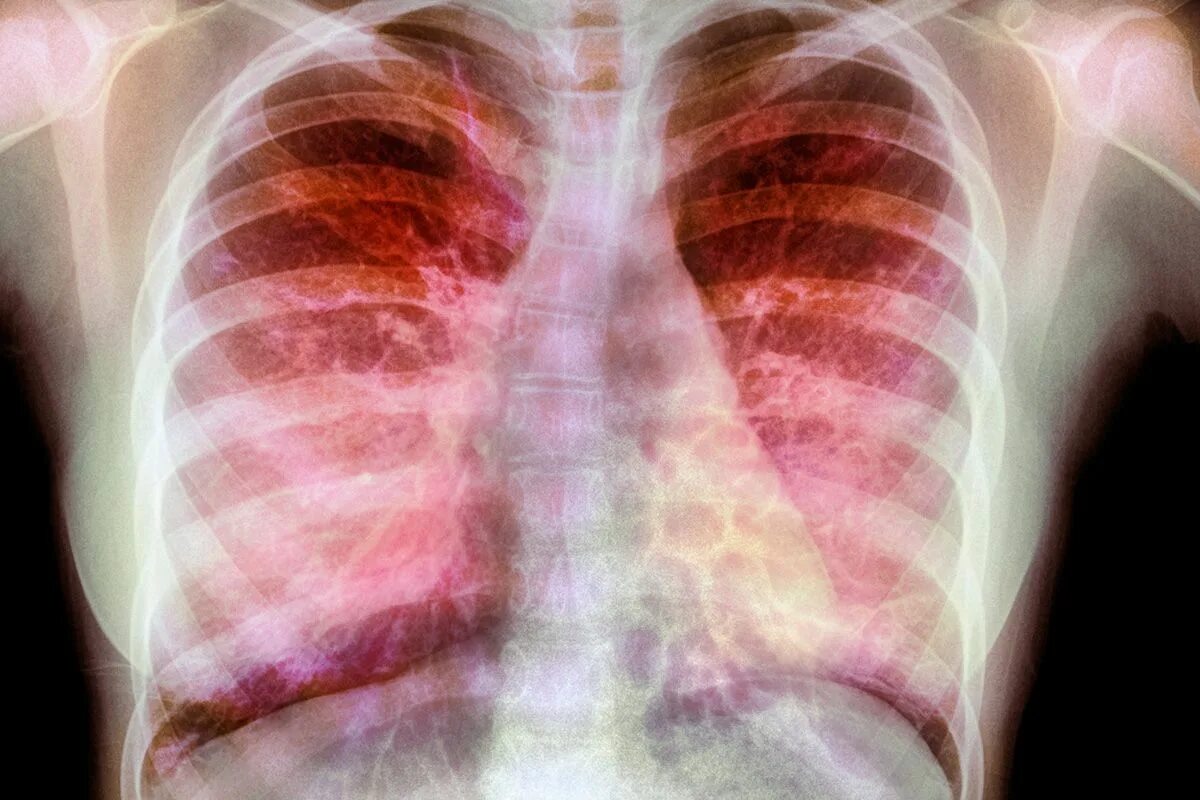

Фиброзное заболевание легких